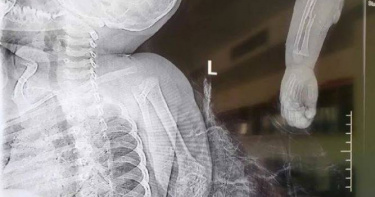

手伸狗籠遭藏獒狠咬…1歲半男嬰「右臂當場扯斷」 醫花6小時接回

大陸江西省醫學科學院附屬嘉佑曙光骨科醫院日前收治了一位1歲6個月大的男童康康(化名),他的手臂被家中飼養的藏獒咬斷,傷勢十分嚴重。醫生緊急為傷者進行手術,目前斷掉的肌肉、肌腱、骨頭都已重新接上,再植肢體的血液流通還算良好,但仍需要在加護病房進一步觀察。綜合陸媒報導,江西省醫學科學院附屬嘉佑曙光骨科醫院手足外科主治醫師龔小濤透露,今年1歲半的患者張某來自宜春市上高縣,當時家長說孩子是被家養藏獒咬傷,「小孩子把手伸到籠子裡面去了,然後被狗咬的。」由於男童傷勢嚴重,家人選擇將他從老家宜春送到南昌接受治療。龔小濤表示,傷者的神經、肌肉撕脫,手術差不多花了6個小時,上肢的三大神經、斷掉的肌肉、肌腱、骨頭都已經接上去了,目前來說,再植肢體的血運還是良好的。至於手臂功能最終會受到多大影響,醫生說明,要看後續的康復情況而定。龔小濤指出,從醫院接診量來看,肢體離斷傷多見於工傷,近年來逐漸減少,兒童肢體離斷的情況並不多見;如果發生肢體離斷損傷,在就醫前需要正確保存好離斷肢體,應使用無菌敷料或清潔布料、毛巾等包裏,並以低溫方法保存,但不可用任何液體浸泡,盡快送醫,缺損時間越長,組織壞死的量就越大。